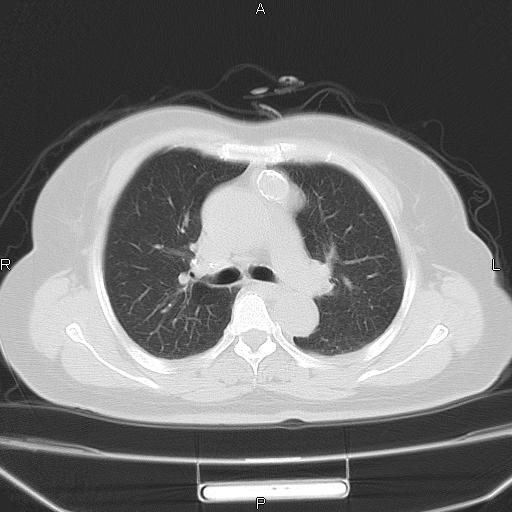

胸腺瘤

女、63Y 双眼睑下垂,早轻晚重。 胸腺瘤???

结果胸腺瘤